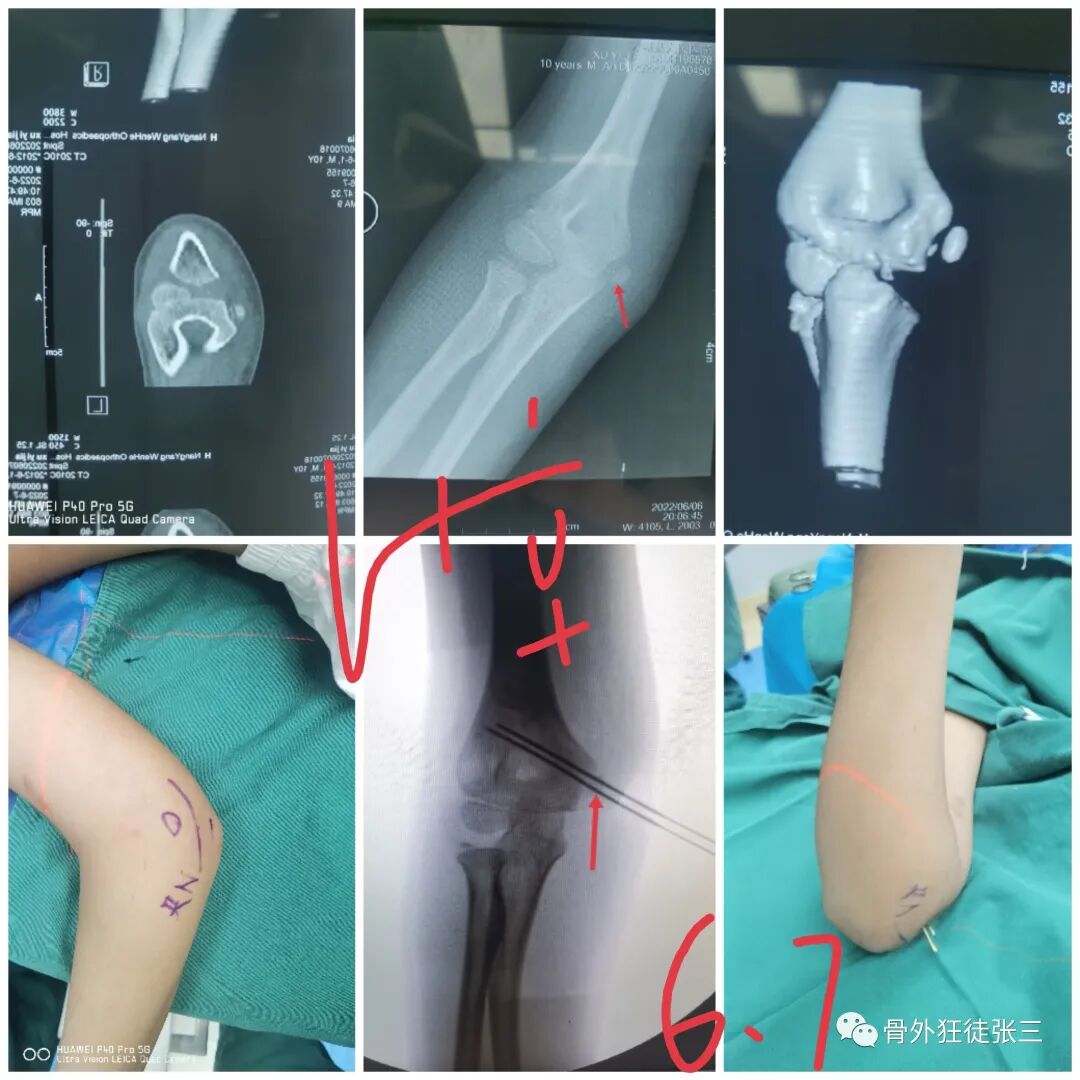

病例14,儿童髁上骨折零切开,桡侧三枚针发散固定

病例15,儿童髁上骨折零切开,

病例16,儿童髁上骨折零切开

病例17,低位髁上骨折零切开

病例18,第一掌骨基底部骨折,闭合复位,克氏针支架